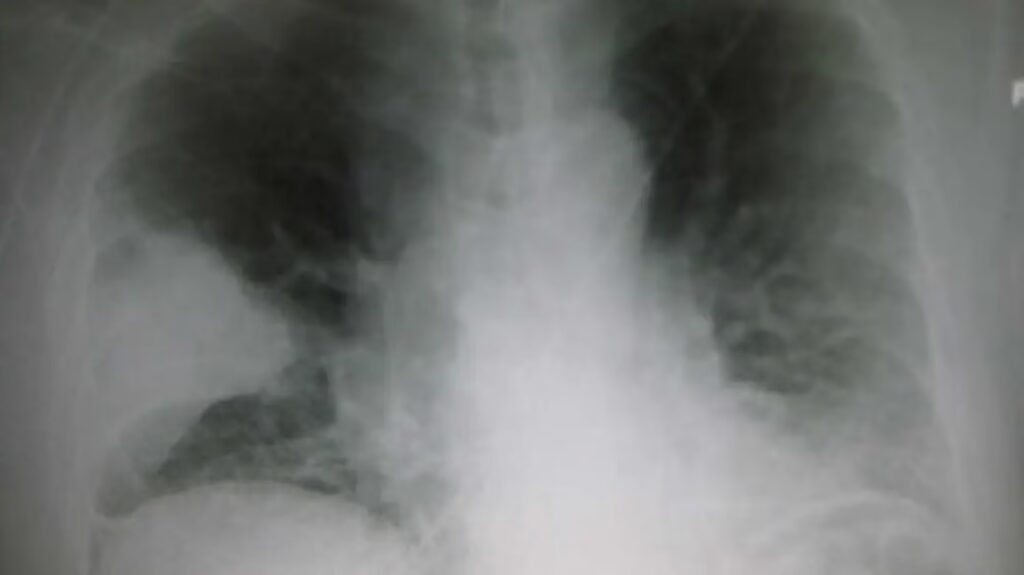

Når en læge nævner termen lungekonsolidering, refererer de til en tilstand, hvor de små luftsække i lungerne, kendt som alveoler, bliver fyldt med væske i stedet for luft. Dette kan være pus, blod, vand eller andre stoffer. Resultatet er, at en del af lungevævet bliver tæt og solidt, hvilket er tydeligt på billeddiagnostiske undersøgelser som et røntgenbillede af brystkassen eller en CT-scanning. En sund lunge fremstår mørk og luftfyldt på disse billeder, mens et konsolideret område vil se hvidt og solidt ud. Det er vigtigt at forstå, at konsolidering ikke er en sygdom i sig selv, men snarere et tegn på en underliggende medicinsk tilstand, der kræver opmærksomhed og behandling. At identificere årsagen til konsolideringen er afgørende for at kunne iværksætte den korrekte behandling og forbedre patientens prognose.

Den absolut hyppigste årsag til lungekonsolidering er lungebetændelse. Dette er en betændelsestilstand i lungevævet, som oftest er forårsaget af en infektion med bakterier, vira eller svampe. Når kroppens immunforsvar reagerer på infektionen, sendes hvide blodlegemer og væske til det inficerede område. Denne ophobning af betændelsesceller, væske og affaldsprodukter fylder alveolerne og skaber konsolidering. Lobær pneumoni er en type, hvor en hel lungelap er påvirket, hvilket giver et meget tydeligt billede af konsolidering på et røntgenbillede.

Atelektase refererer til et delvist eller komplet kollaps af lungevævet. Dette sker, når de små luftveje bliver blokeret, ofte af slimpropper, eller når der er et eksternt tryk på lungen. Uden luft kan alveolerne ikke holde sig udfoldede og klapper sammen. På et røntgenbillede kan et område med atelektase ligne konsolidering, og det kan være svært at skelne fra f.eks. lungebetændelse, især fordi de to tilstande ofte forekommer samtidigt hos patienter med de samme risikofaktorer.

- Røntgenbillede af brystkassen: Dette er ofte den første undersøgelse. Det kan tydeligt vise de hvide, tætte områder af konsolidering.